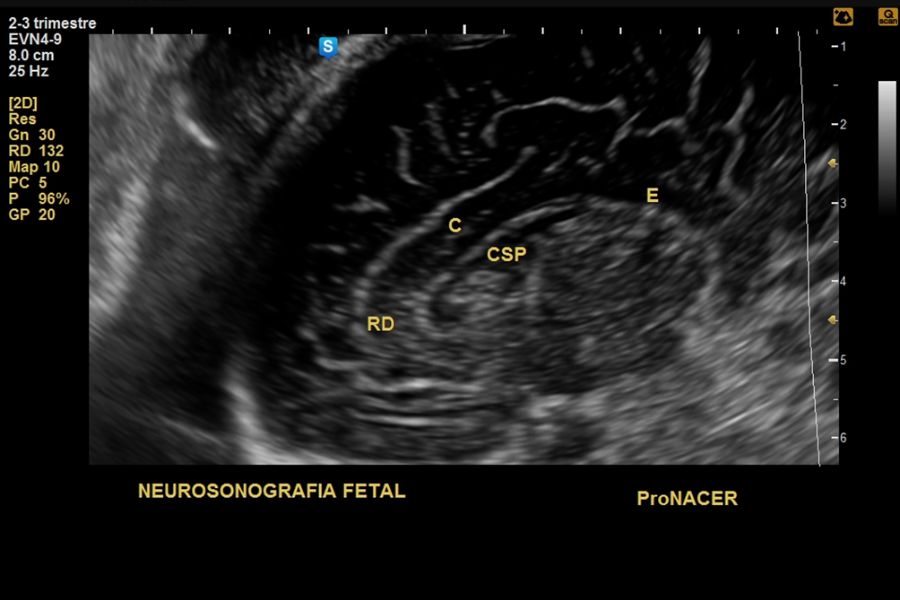

Neurosonografía fetal : Desde las 20 a 41 semanas

Neurosonografía fetal: Desde las 20 a 41 semanas